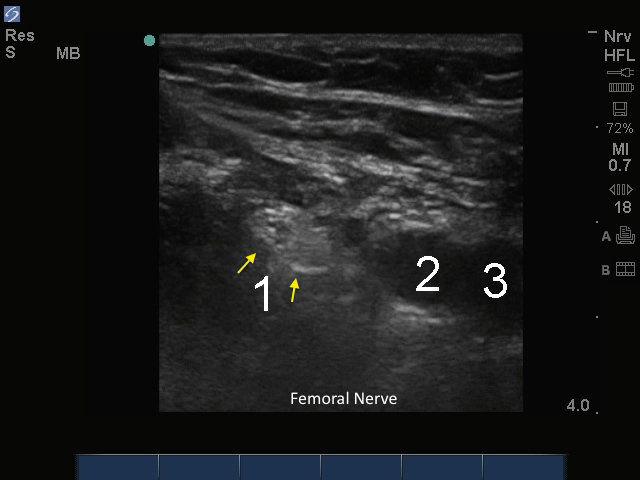

M-Turbo: Nervus und Arteria femoralis

1. Nerve (Nerv)

2. Arterie

3. Vene